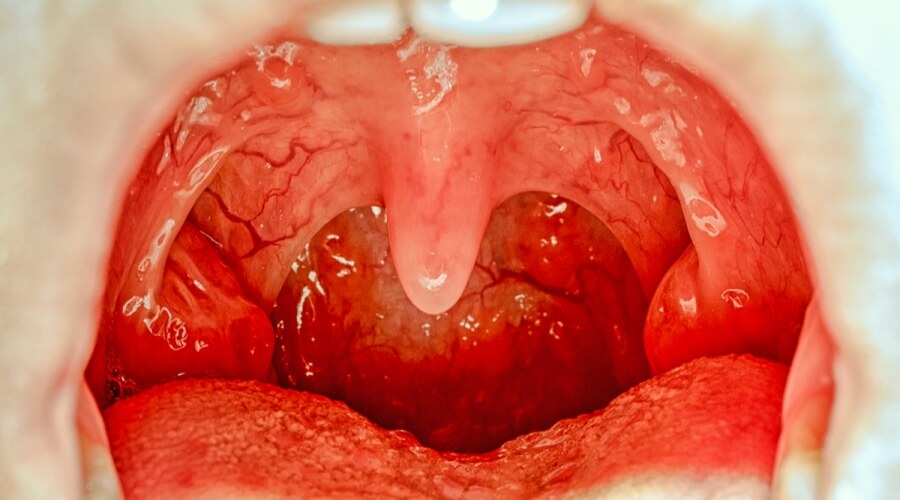

تُعرَف اللوزتان على أنَّهما عُقدتان لمفاويَّتان لهما وظيفة دفاعيّة في الجسم ضِدَّ أيِّ عدوى، وقد تُؤدِّي إصابة اللوزتَين بأيِّ عدوى إلى حدوث التهاب باللوزتَين (بالإنجليزيّة: Tonsillitis)، والذي ينتشر لدى الأطفال، وقد يتسبَّب بالتهاب اللوزتين العدوى الفيروسيّة، أو البكتيريّة، كما تُسبِّب إصابة اللوزتَين بالاتهاب ظهور العديد من الأعراض التي قد تستمرُّ عادة من 7-10 أيّام، وتتشابه معظم الأعراض في التهابات اللوزتَين سواءً كانت مُزمنة، أو غير مُزمنة، ومن هذه الأعراض ما يأتي:

انتفاخ اللوزتَين، واحمرارهما.

هنالك بعض الأعراض التي يتميَّز بها التهاب اللوزتَين المُزمن (بالإنجليزيّة: Chronic tonsillitis)، ومن هذه الأعراض:

الإصابة بالتهاب الحلق المُزمن.

ينتشر التهاب اللوزتَين المُزمن لدى فئة المراهقين، والبالغين؛ إمّا بسبب عدوى بكتيريّة مقاومة للمُضادَّات الحيويّة، أو مشاكل مُتعلِّقة بجهاز المناعة، أو التعرُّض للعلاج الإشعاعيّ، ويُعَدُّ العلاج الأوَّلي لالتهاب اللوزتَين المُزمن السيطرة على الألم عن طريق استخدام مُسكِّنات الألم، مثل: الأسيتامينوفين، والإيبوبروفين التي لا تحتاج إلى وصفة طبِّية، حيث تُحافظ هذه الأدوية أيضاً على رطوبة الفم، وتحدُّ من جفافه، وفي حالة الإصابة بالتهاب اللوزتَين خمس إلى سبع مرَّات في السنة، فيجب إجراء الجراحة لإزالة اللوزتَين، حيث تُقلِّل هذه الجراحة من عدد مرَّات التهاب الحلق، وأيضاً من عدد المُضادَّات الحيويّة المُستخدَمة سنويّاً، وتُحسِّن الحياة اليوميّة، حيث يُؤثِّر التهاب اللوزتَين في طبيعة الحياة.